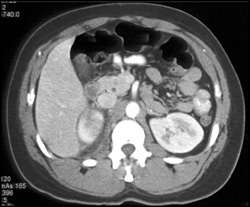

Transitional Cell Carcinoma Left Kidney